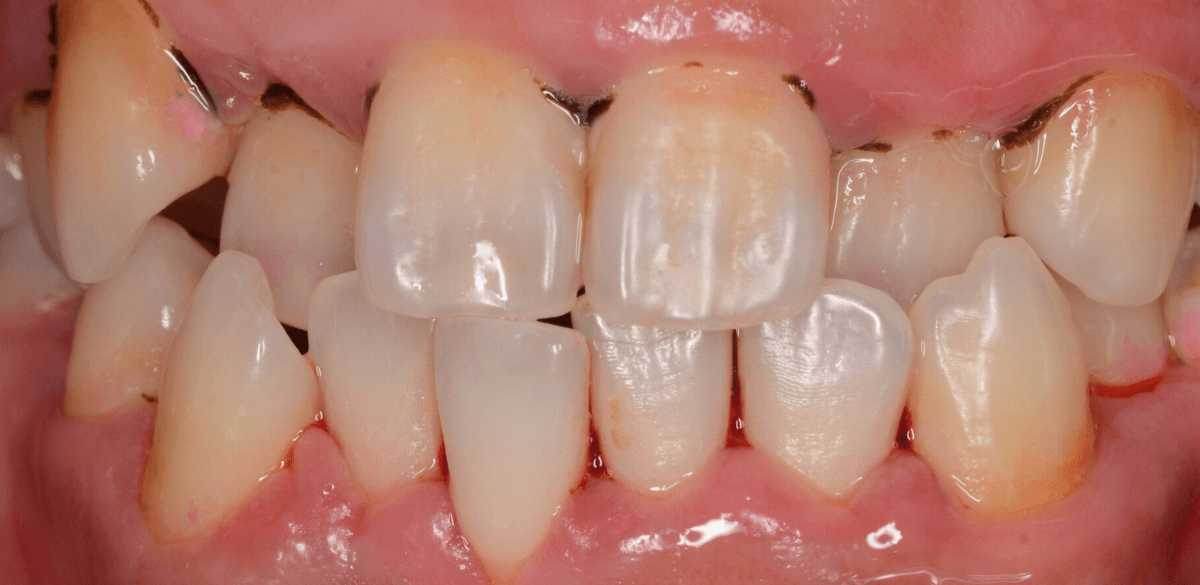

ビフォー・アフターです。

後日、上の前歯の歯石除去を行いました。

下の前歯の歯肉も改善されてきていますね。

上の歯だけで、これだけの縁下歯石がとれました(まだ歯肉の奥には残っていると思います)。

一度では取り切れません、時間をかけて取っていく必要があります。

かなり歯肉の改善がされていますが、まだしばらく治療は続ける必要があります。